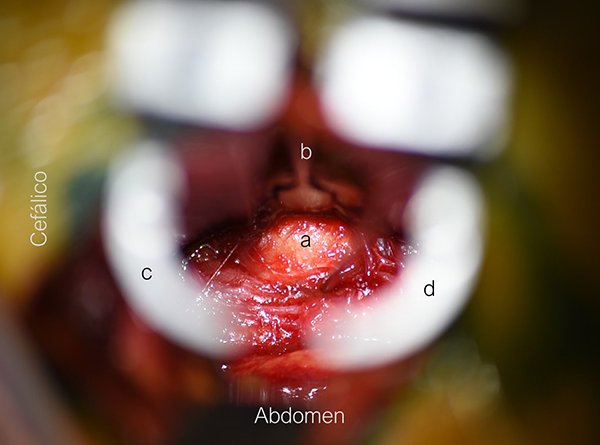

Colocación del separador

Identificado el corredor quirúrgico, la aguja iniciadora es colocada para confirmar el nivel con radioscopia. Utilizamos el dedo índice para descender la aguja protegiendo las estructuras vasculares y viscerales, colocando la misma en la unión del tercio anterior con el tercio medio del disco.9 Si la radioscopía confirma el adecuado posicionamiento, se realiza la colocación de los dilatadores secuenciales y finalmente del separador tubular. El separador de 2 valvas se coloca de forma tal que se realice una apertura en sentido craneocaudal. Para esto las valvas deben estar colocadas paralelas a los platillos vertebrales, evitando compresiones del plexo lumbar asociadas a aperturas anteroposteriores. De ser necesario, un separador manual puede utilizarse para retraer suavemente el psoas hacia posterio,10 con la precaución de no superar el plano medio del músculo para evitar la lesión del nervio genitofemoral (localizado en la cara anterolateral del psoas), y el plexo lumbar (Figura 5).

Figura 5: Imagen intraoperatoria con la colocación final de los separadores. a) Disco intervertebral. b) separador manual con retracción del psoas. c y d) Valvas cefálica y caudal respectivamente.